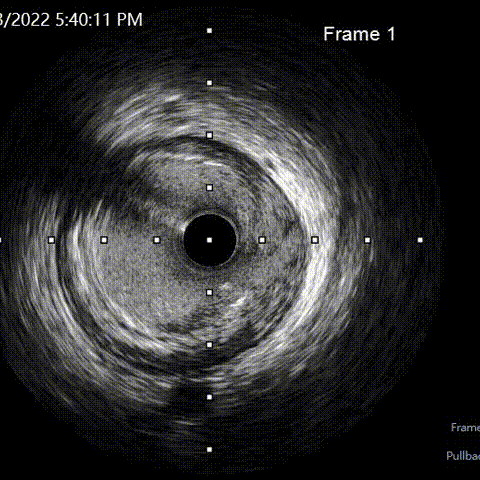

LAD pre-IVUS check RUN 1 looking for entry point

Ballon 2.5*15mm, 3.0*15mm Dilatation & IVUS check

LAD pre-IVUS check RUN 2

LAD post-IVUS check RUN 3

首选IVUS找开口、因LM直径达6.5mm,无法看清分支方向。